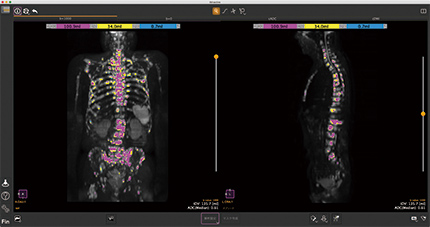

BD-Score

全身DWIから高信号領域の自動抽出機能を搭載し、ステーション統合までフルオート。ADC値の中央値など多数の統計指標を算出。解析は10秒程度で完了します。